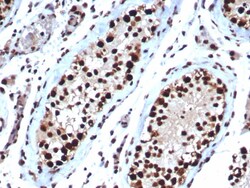

HspA1B Antibody (HSPA1B/7623), Novus Biologicals™

| Dilution | Western Blot : 1-2 μg/mL, Immunohistochemistry-Paraffin : 1-2 μg/mL |

| Applications | Western Blot, Immunohistochemistry (Paraffin) |

HspA1B Monoclonal antibody specifically detects HspA1B in Human samples. It is validated for Western Blot, Immunohistochemistry (Paraffin)Specifications

| FLJ54328, Heat shock 70 kDa protein 1/2, heat shock 70 kDa protein 1A/1B, heat shock 70kD protein 1B, heat shock 70kDa protein 1B, HSP70.1/HSP70.2, HSP70-1/HSP70-2, HSP70-1B, HSP70-2, HSPA1, HSPA1A | |